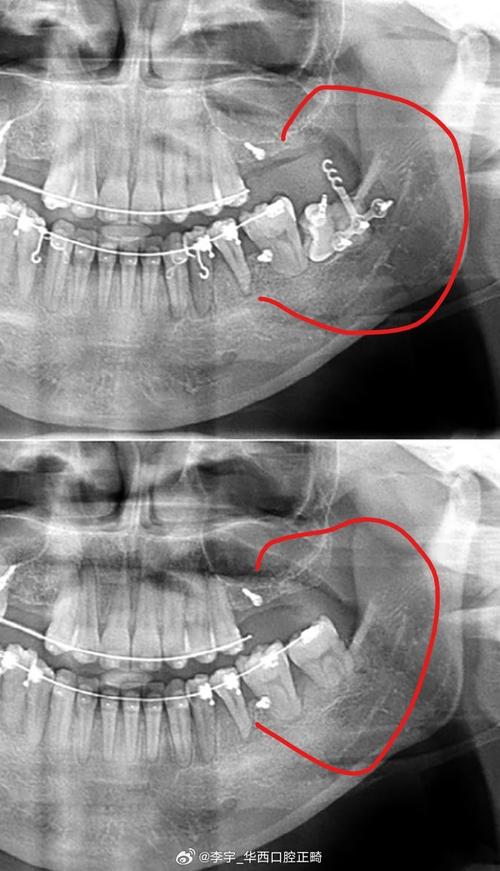

低位水平阻生齿的正畸治疗核心在于“解除阻生、引导萌出、保存功能”,通过科学设计牵引路径,将埋藏的牙齿移动至正常咬合位置,避免邻牙损害及颌骨破坏,治疗前需全面评估:临床检查需观察口腔黏膜状况、邻牙松动度及咬合关系;影像学检查是关键,通过CBCT可清晰显示阻生牙的萌出方向、牙根形态、与邻牙牙根及下颌神经管的距离,判断是否具备牵引条件;同时需研究模型分析咬合曲线,制定个性化方案。

在局麻下于阻生牙牙冠顶部切开黏膜,去除部分骨质,暴露牙冠并粘接牵引钩,随后用镍钛丝或橡皮圈将牵引钩与矫治器连接,施加轻柔持续的力量(50-70g),每周复诊调整牵引方向,牵引过程中需密切观察牙根吸收情况,若出现明显吸收,需暂停牵引或调整力值。